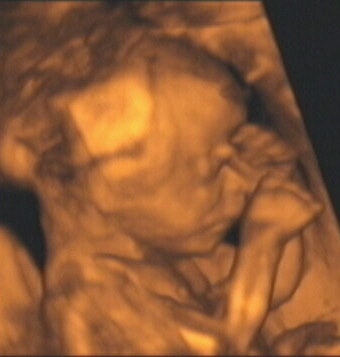

![]() |

| Figure 8, a 3-D ultrasound image of a fetus with hands in front of face at 21 weeks gestation. Image courtesy of Stefano Ciatti, M.D. |